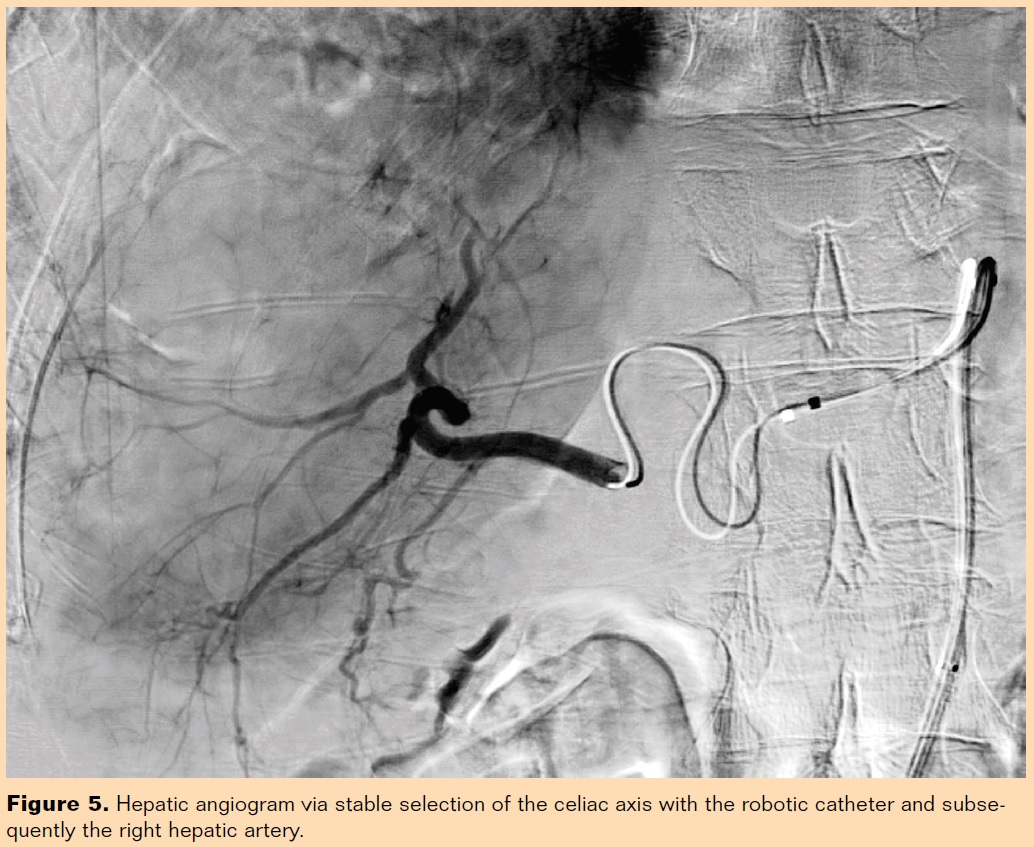

The robotic catheter can be especially helpful in the setting of very tortuous aortoiliac anatomy with significant angulation of the celiac axis or superior mesenteric artery that can make manual catheterization difficult or impossible. Although these represent a minority of cases, such cases sometimes necessitate utilization of an upper-extremity approach. The robotic catheter allows for excellent stability from a femoral approach, enabling stable catheterization of targeted vessels because of the ability to manipulate the catheter into different shapes and angles (Figures 4 and 5).

We have not encountered any complications with robot-assisted hepatic embolization procedures. In fact, we have not encountered any complications with the robot for any vascular procedure. Prior to the FDA clearance of the 6 Fr robotic catheter (Figure 6), we performed chemoembolization with the 9 Fr catheter. The clearance of the 6 Fr catheter was a significant advancement as it allowed the procedure to be performed via a smaller profile 6 Fr sheath, which is the size catheter that we generally use. Although we did not encounter any groin complications when utilizing a 9 Fr sheath, the smaller 6 Fr catheter is likely safer. The 6 Fr robotic catheter is designed to catheterize and intervene in smaller vessels. Robotic catheterization is currently limited for smaller vessels for which the smaller 6 Fr system is often still too large and often requires delivery of a microcatheter through the robotic system. Hansen Medical is currently investigating smaller catheters that would be valuable in selecting and tracking into smaller vessels in this setting. We are excited about the future of robotic-guided microcatheters, which will further increase the utility of this system for embolization procedures as well as other peripheral interventions.